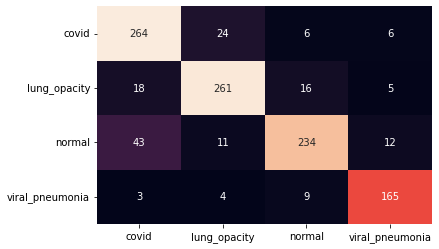

III.2 Classification results

The training procedure in all scenarios has converged. Looking at the evolution of training and validation accuracy (Fig. 11a) indicates that a larger validation dataset would be beneficial. To stabilise the classifier training a procedure of multiple training runs to select the best model is used (Materials and methods). Resulting classifiers are able to discriminate between classes with good precision, for example, see the confusion matrix of the best overall model presented in Fig. 11b. It can also be seen that for the normal class, the rate of misclassified images as COVID-19 ones is higher than for other classes. This effect is present for all models although smaller for the ones based on the EfficientNet-B0 architecture. In addition, the EfficientNet-B0 variants excel if the correct classification of viral pneumonia class images with the smallest rate of errors. However, the EfficientNet-B0 GAN augmentation scenario shows increased misclassification of healthy images which leads to a poor performance. The evolution of the training accuracy as well as confusion matrices for all models are summarised at the end of this section.

The results of the best-trained model for each of the four scenarios are analysed using a number of popular metrics. As presented in Table 2 the most accurate model, based on multiple metrics, is an EfficientNet-B0 trained on the balanced dataset. Obtained accuracy of is in line with results obtained by Khan E. et al. Khan et al. (2022) i.e. accuracy using classical augmentation and standard transfer learning with EfficientNet-B1 or accuracy with a modified approach.

In the case of Inception-v3, all scenarios that lead to a more balanced dataset have a significant advantage over the raw unbalanced sample. Including GAN augmentation where an accuracy increase of points is observed. The most accurate classifier is obtained in a classical augmentation scenario. For EfficientNet-B0 result obtained without augmentation is very precise and only a small improvement is observed from the balancing of the training data. The inclusion of GAN-based augmentation leads to a deterioration of accuracy.